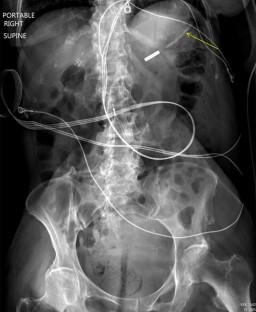

Fig. 1